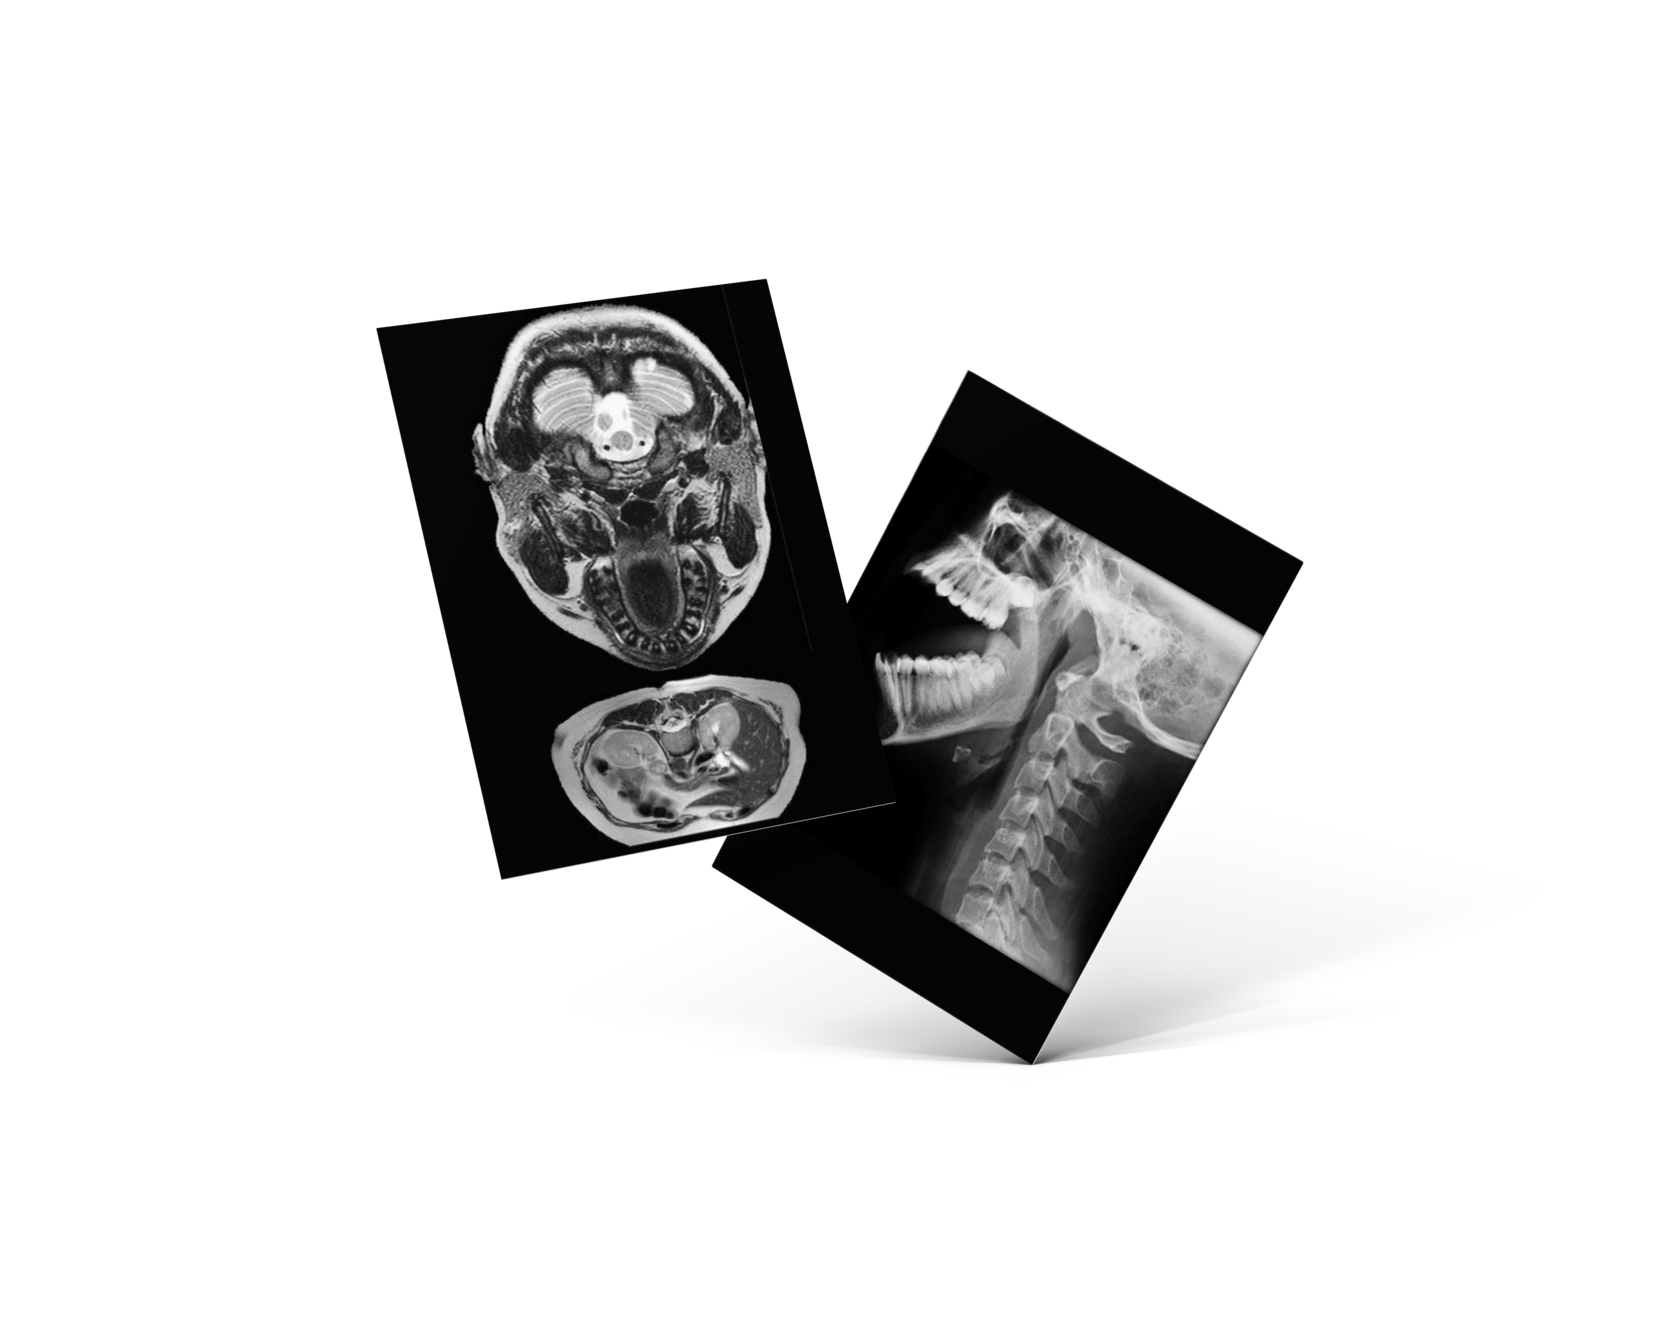

КЛИНИЧЕСКИЕ РАЗБОРЫ МРТ ВНЧС ОРТОДОНТИЧЕСКИХ ПАЦИЕНТОВ

Как научиться интерпретировать данные исследования МРТ в повседневной практике стоматолога-ортодонта

1. Будут разобраны исследования МРТ ВНЧС пациентов перед ортодонтическим лечением

2. Научитесь читать МРТ ВНЧС исследования и использовать их в повседневной практике

3. Научитесь находить положения диска и мыщелка с открытым и закрытым ртом

4. Получите понимание зачем нужно отправлять ортодонтического пациента на исследование МРТ ВНЧС